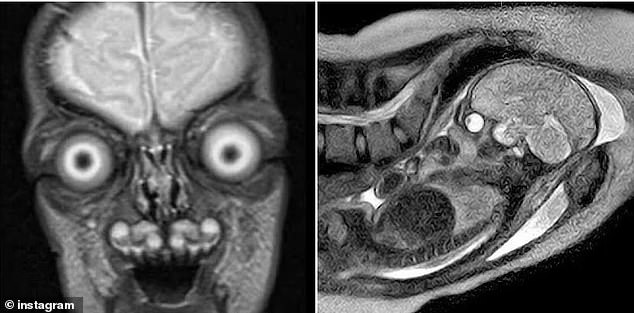

Disturbing images of fetal MRIs have resurfaced online, sparking renewed debate about the safety and necessity of the procedure during pregnancy. These scans reveal an unsettlingly clear view of a fetus's anatomy, with bones appearing as stark white against darker tissue. The skeletal structure, including the spine, ribs, skull, and even individual finger bones, stands out in sharp detail. Eyes, filled with fluid, appear as dark, hollow sockets that sometimes seem to bulge or stare outward, evoking a sense of eerie realism. For expectant mothers, such images can be profoundly unsettling, raising concerns about potential risks and long-term effects.

Public reactions to shared MRI images often range from fascination to fear. Online commenters have described the scans as both terrifying and strangely captivating, with some users expressing disbelief at the images' realism. Yet despite these mixed reactions, data from a 2023 study of 156 pregnant women reveals a significant willingness to undergo MRIs when medically indicated. Eighty percent of participants would opt for an MRI if prescribed by a doctor to diagnose a potential issue, but only 24 percent were open to participating in MRI research. This highlights a clear divide in public perception, with most women prioritizing medical necessity over curiosity.